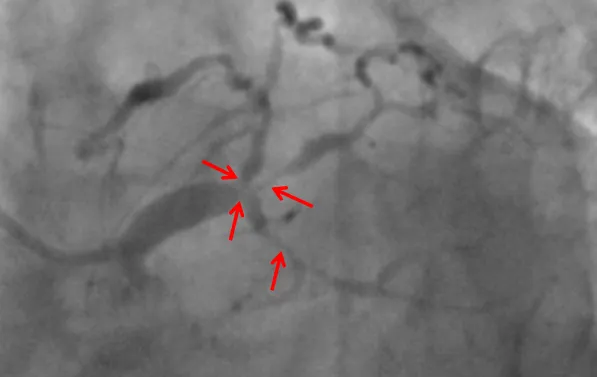

近日,小妲己直播app (简称小妲己直播app )心血管内科联合重症医学科、心胸外科等科室,在ECMO器械辅助下,为一名复杂高危冠脉病变患者进行了精准冠脉介入治疗,开通病变冠脉血管。目前患者已康复出院。该项技术的开展,标志小妲己直播app 对高危复杂患者治疗技术又迈上一个新台阶。患者“心悬一线”辗转多家医院就医无果据了解,69岁的张先生(化名)一年来总是感觉胸口闷胀不适,尤其是上楼、快步...